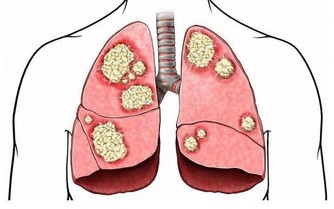

日前一名16歲腦性麻痺少女因發燒3天、食欲不振、便秘且嚴重貧血而就醫,經過進一步檢查,才發現少女已經大腸癌末期無法再做積極治療,僅能做症狀治療舒緩其不適。近幾年來大腸癌有年齡層下降的趨勢,專家建議家長特別留意孩子症狀,才能有助及早發現、提早治療。

據《自由時報》報導,這名罹病少女無家族病史,體重較同齡者輕且飲食上並無特別偏重,攝取高油脂及刺激性的食物,但由於少女本身有表達上困難,導致症狀更不易發現,一旦發現,為時已晚。

專家提醒人們要重視腸癌發病率呈年輕化趨勢。兒童如出現腹部不適、不明原因的腹痛、大便習慣改變、便中帶血和黏液時要想到結腸癌的可能,儘早到正規醫院就診,爭取早期診斷、早期治療。

大腸癌多見於40歲以上的中年人,發生在兒童則十分少見。由於結腸癌起病較隱匿,早期癥狀不明顯,且無特異性,加之人們不易想到兒童能患結腸癌,往往易誤診為其他疾病。所以兒童結腸癌易延誤診斷,就診時常屬晚期,且常並發腸梗阻,預後較差。